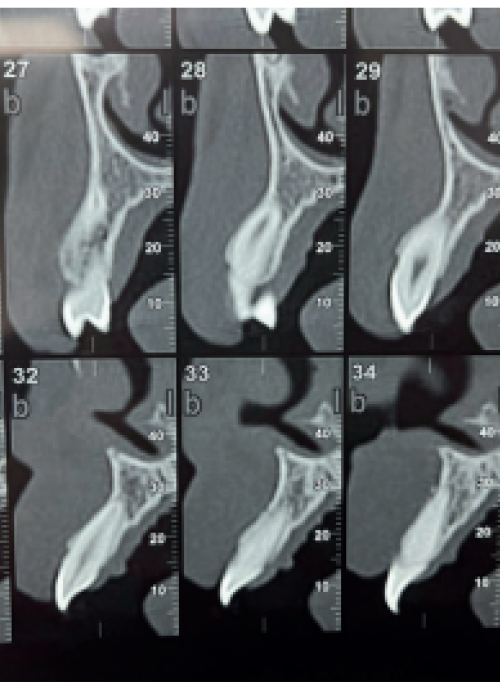

Evaluación de la cantidad de hueso neoformado al emplear materiales de relleno en elevación de seno maxilar con abordaje lateral